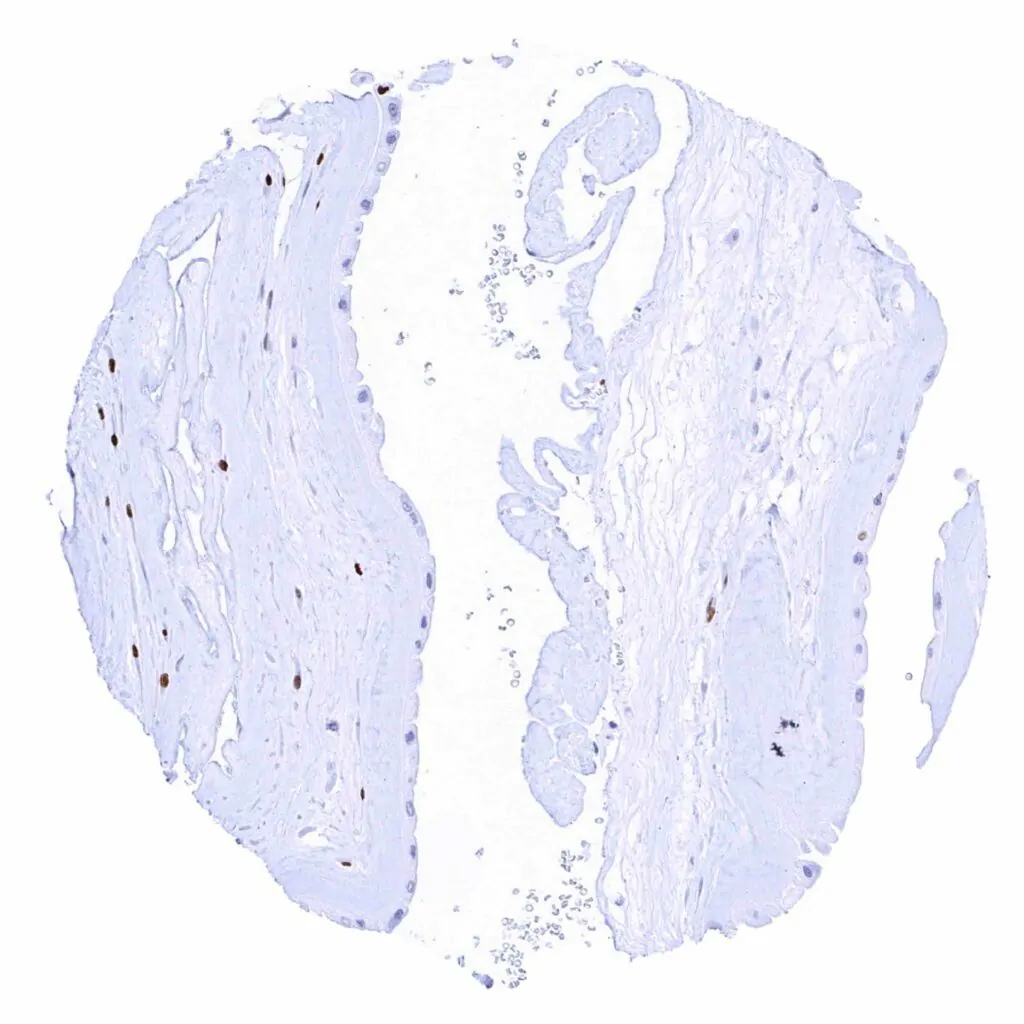

Aorta, media